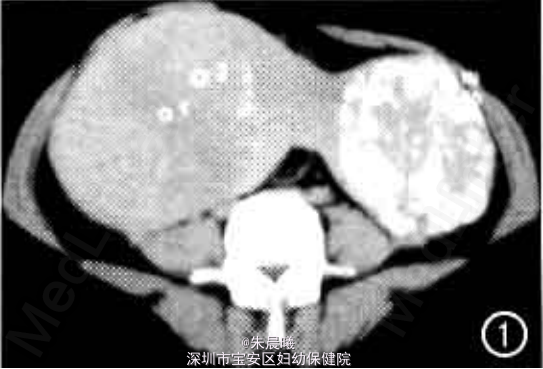

查体:腹膨隆,可触及盆腔包块达脐上两横指,质硬、无压痛,子宫及附件扪及不清。 实验室检查无异常。 静脉肾盂造影见中下腹13 cm×24 cm和11 cm×13 cm大小包块,呈哑铃状,边缘界限清楚。左侧包块内布满爆米花样钙化,输尿管受压右移,未见阻塞;右侧积尿系轻度扩张,膀胱左侧受压变形,CT平扫加增强如图1、2。

诊断:盆腔包块待查:子宫肌瘤? 治疗:此病例予开腹手术,手术见子宫巨大肿瘤及右侧附件阔韧带区肿瘤,肿物与子宫底有索条状蒂相连,大小分别为30 cm×20 cm×20 cm和12 cm×12 cm×12 cm,重3妇,实性,有包膜。病理诊断:①子宫多发性肌瘤,可见玻璃样变;②慢性宫颈炎;③(右)卵巢、输卵管组织。

随访:子宫多发肌瘤易反复,约1/3患者需再次手术,术后定期复查B超。 讨论:子宫肌瘤90%以上生长于子宫体部,仅有4%~8%发生于子宫颈,且多在后唇。在体部者多长于子宫底,后壁次之,位于前壁者比后壁少一半,而以两侧者最少。肌瘤的类型以壁问肌瘤最多,浆膜下肌瘤次之,粘膜下肌瘤比较少见。本例盆腔巨大包块为多发浆膜下肌瘤,并向右侧附件阔韧带区伸展,带蒂,形成阔韧带肌瘤,实性部分内可见不规则钙化。阔韧带平滑肌瘤少见,CT表现为密度均匀或不均匀的软组织肿块,CT值与子宫肌瘤相似,增强扫描呈明显强化,坏死、液化部分不强化。本病例由于肿瘤大、肿瘤内部密度不均匀出现爆米花样钙化而误为卵巢病变,遇到类似病例表现,要想到浆膜下子宫肌瘤可向子宫旁伸展或向周围寄生。